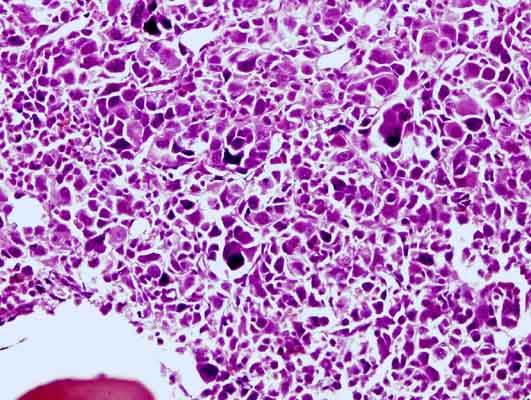

Figure 2. Bone marrow biopsy showing imature cells of variable size and some bone marrow fibrosis (at x 20 magnification).